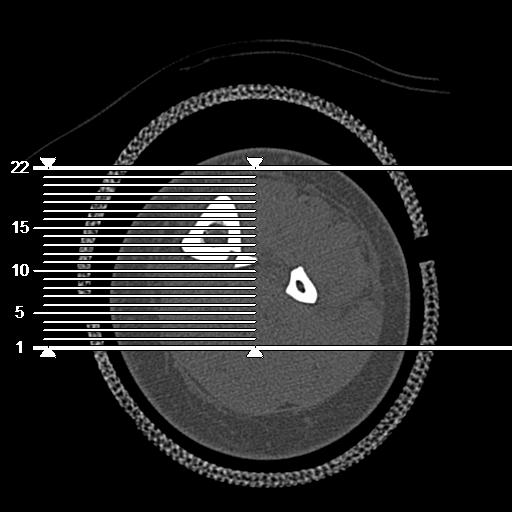

102803 1/12(キウスなし) 1/27 左下腿 4R 30歳女性 左脛骨軸内釘